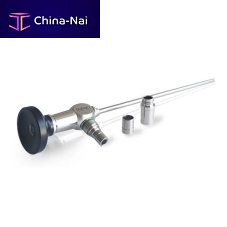

- ENT examination microscope 13